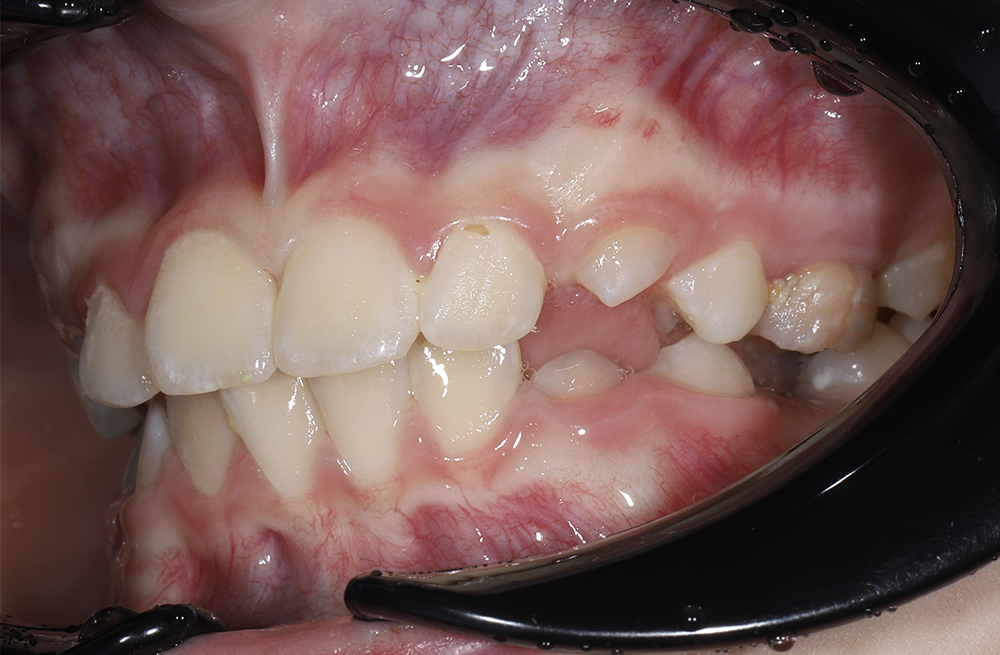

Два этапа ортодонтического лечения у семилетней пациенткиот сложного нарушения прикуса до коррекции положения языка